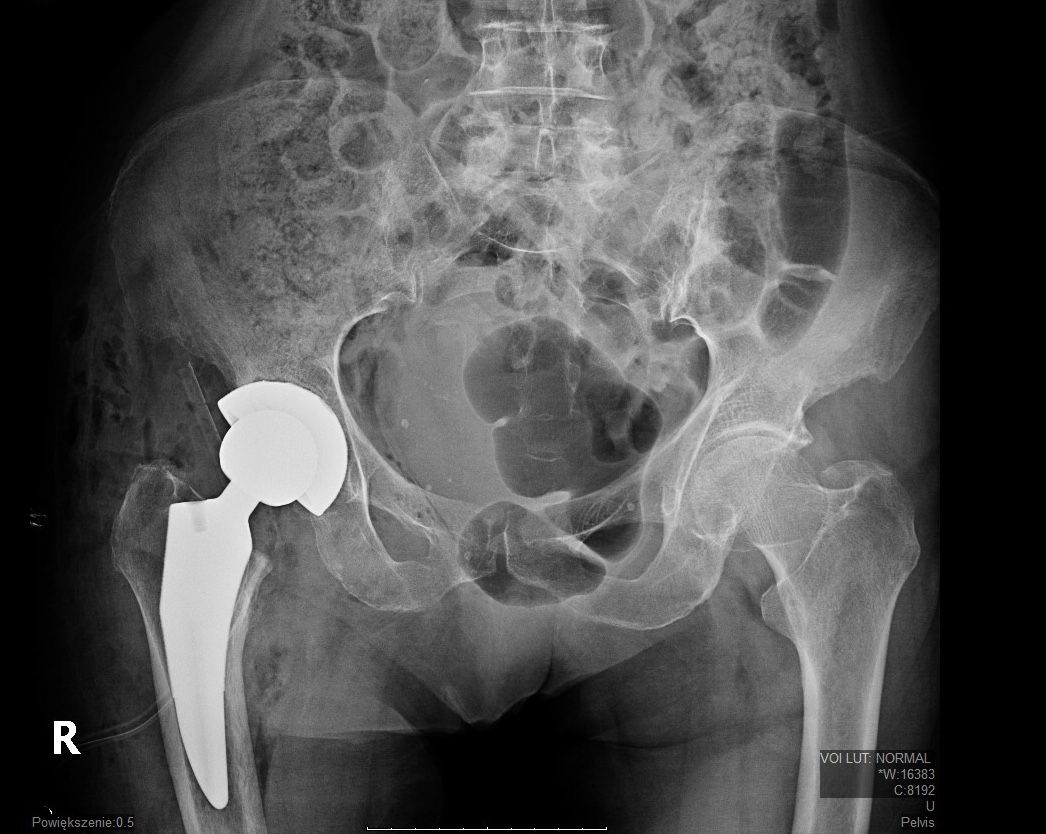

Endoproteza stawu biodrowego

Od 18 000 zł -